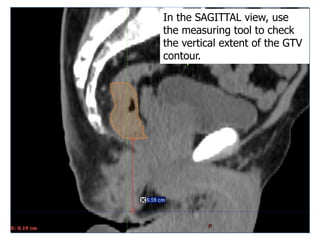

In the SAGITTAL view, use

the measuring tool to check

the vertical extent of the GTV

contour.

24 In the SAGITTALview, use the measuring tool to check the vertical extent of the GTV contour.